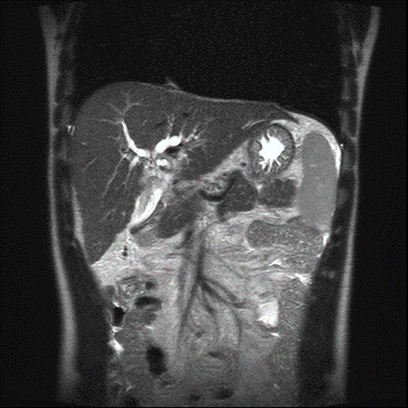

年轻女性多发肝占位:特殊的“棒棒糖”征象指引了怎样的罕见真相?

病史摘要:33岁女性患者,数月来右上腹间歇性不适,伴早饱、腹胀及恶心,症状反复后就诊。 诊疗过程:体格检查无明显异常。实验室检查肝功能及肿瘤标志物正常,尿妊娠试验阴性。腹盆部增强CT见肝内3个不明病灶;腹部MRI显示病灶有包膜皱缩、弥散受限等特征,出现“棒棒糖征”。主要诊断为肝上皮样血管内皮细胞瘤(EHE),鉴别排除转移瘤等疾病。经皮穿刺活检病理及免疫组化确诊EHE。随访8个月病灶大小